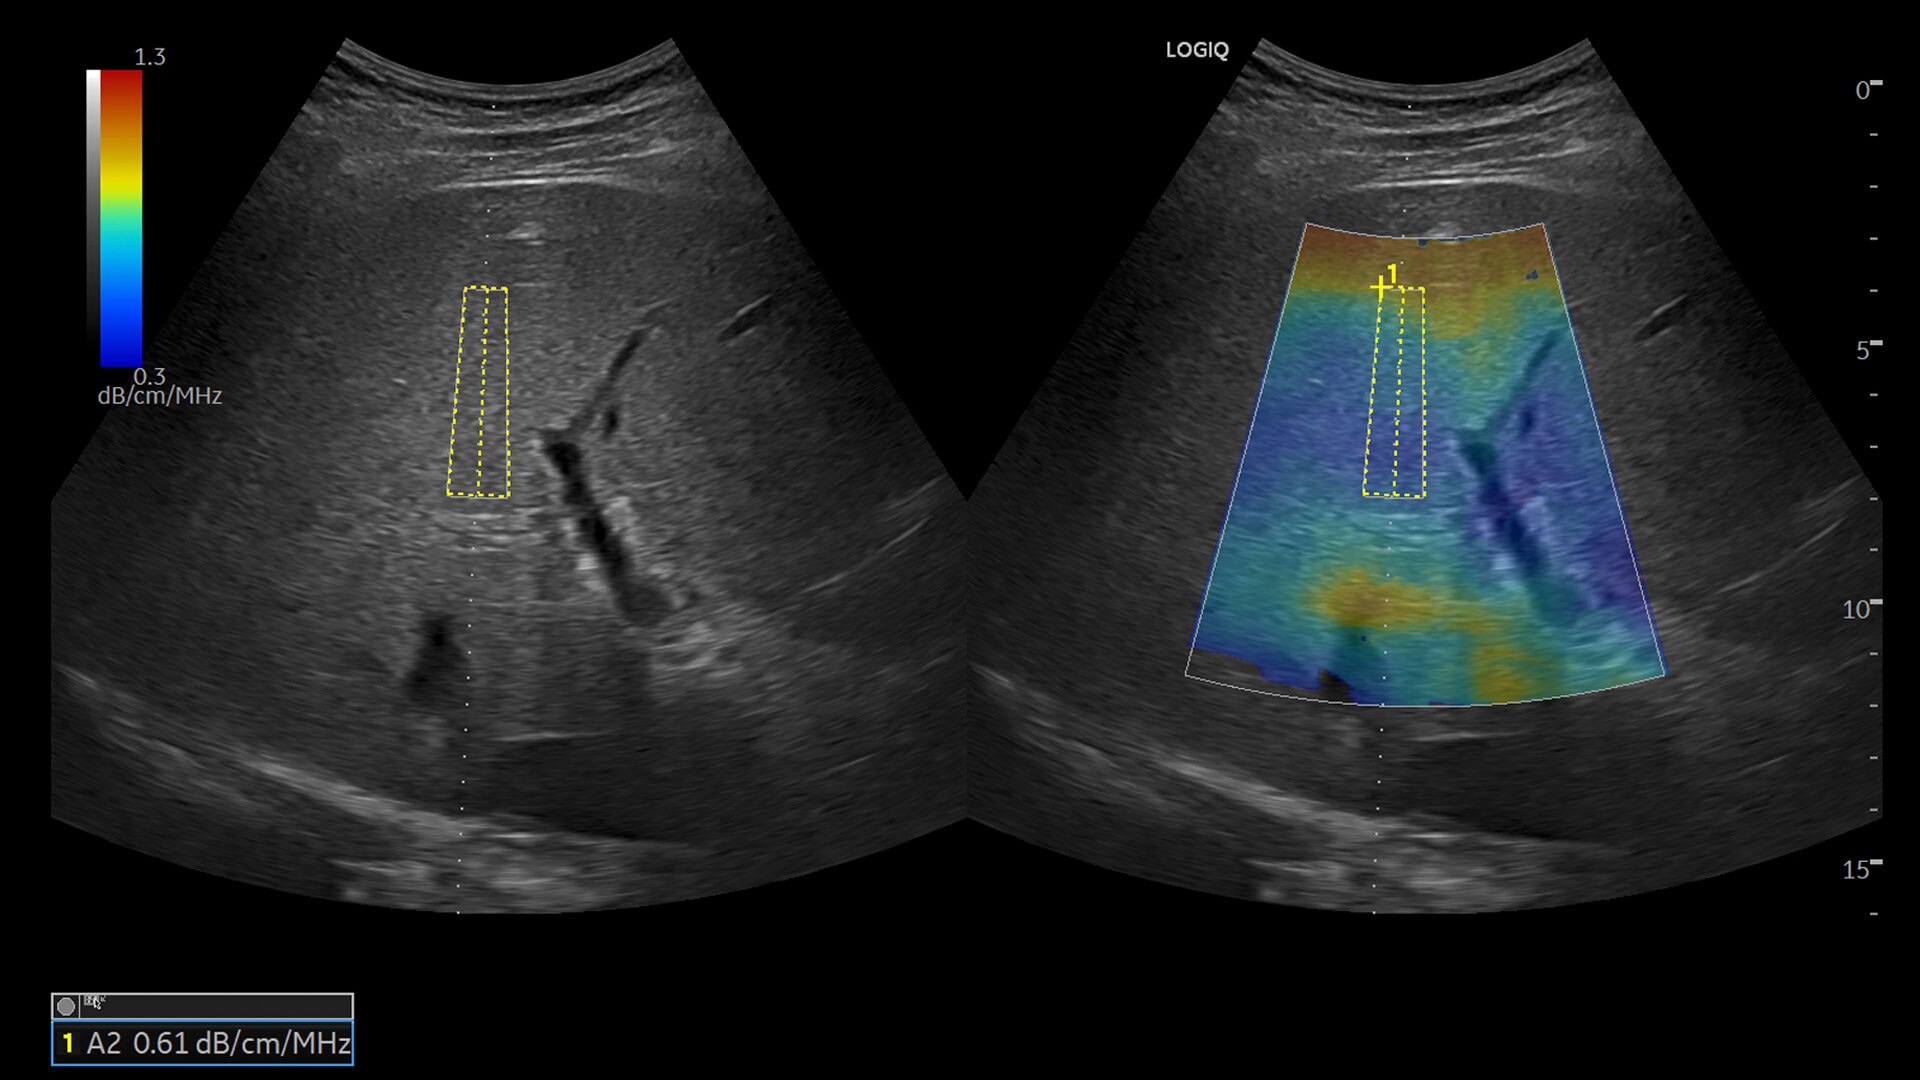

• Ultrasound-Guided Attenuation Parameter (UGAP)

• CEUS